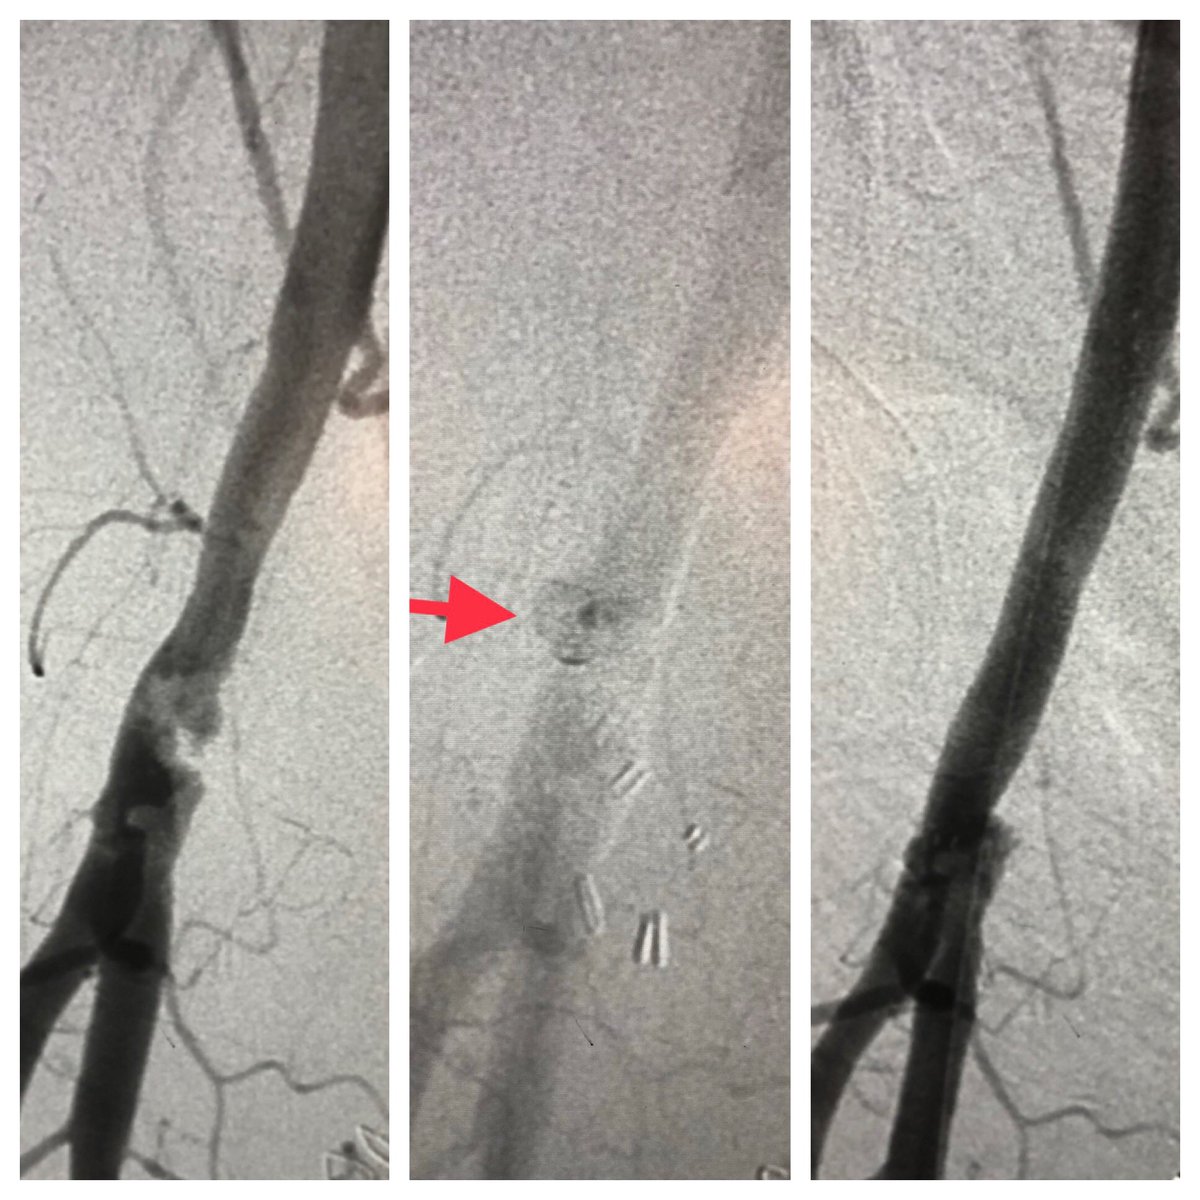

Reminder that femoral complications can be catastrophic. 5fr access site w/ post op bleeding underwent surgical evacuation w/ drain but no bleeding identified. Recurrent bleeding, hypotension and pressors. Barely seen by angio. Treated w/ covered stent #radialfirst #safefemoral